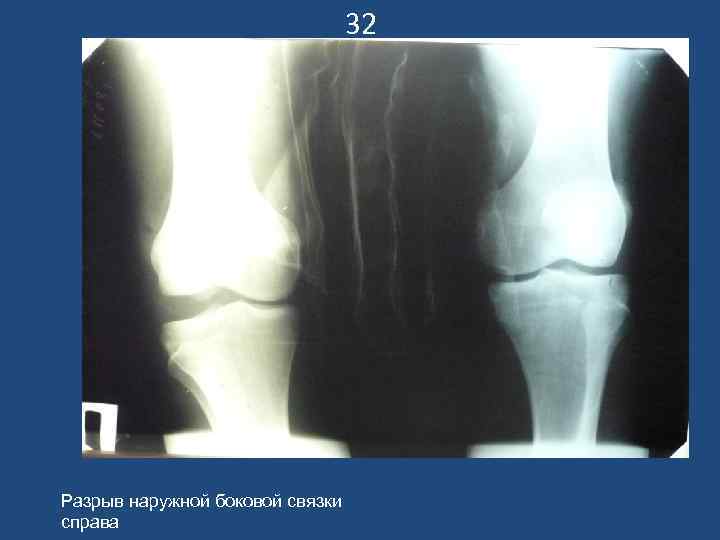

32 Разрыв наружной боковой связки справа